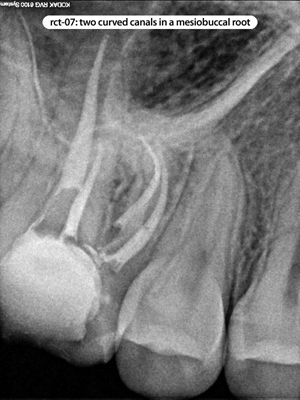

Root Canal Cases